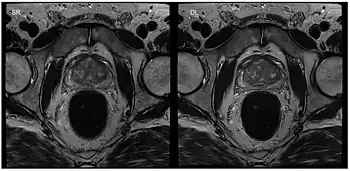

Musculoskeletal MRI

Apart from cardiac MRI other real-time applications deal with functional studies of joint kinetics (e.g., temporomandibular joint,[29] knee and the wrist[30]) or address the coordinated dynamics of the articulators such as lips, tongue, soft palate and vocal folds during speaking (articulatory phonetics)[31] or swallowing.[32] Musculoskeletal imaging in particular benefits from real-time observation. Researchers at the NYU Grossman School of Medicine[33] developed a RT-MRI glove for imaging movement of the hand. The glove uses high impedance coils to prevent the generation of eddy currents from rapidly changing magnetic fields and bSSFP for rapid imaging times. High-impedance coils remove the need for specific coil conformations and active gradient shielding.[34]